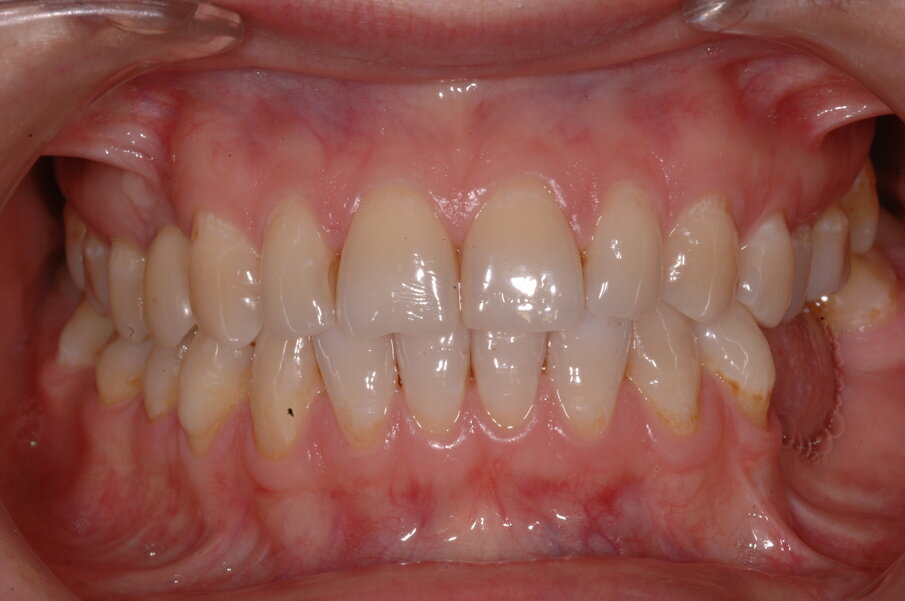

Una paziente di 35 anni si presentò alla nostra attenzione per risolvere un edentulismo parziale nella zona mandibolare inferiore sinistra conseguente all’estrazione traumatica degli elementi 35 e 36 in età scolare (Fig. 1). La paziente all’esame obbiettivo dimostrava un ottima igiene orale con un indice di placca del 7% e un indice di sanguinamento del 5%. L’esame clinico della zona traumatizzata evidenziava una lesione di terza classe di Seibert6 laddove il deficit osseo era caratterizzato da una deficienza nei tessuti duri e molli sia in senso orizzontale che in senso verticale. Risultava significativa anche la scarsa quantità di gengiva cheratinizzata a ricoprire la cresta residua, quantificabile in una banda larga non più di 2 mm (Fig. 2). Una volta eseguita la terapia causale atta a rimuovere il biofilm presente e a preparare la paziente per l’intervento, si procedette a eseguire un esame Cone Beam per approfondire la conoscenza dell’anatomia locale e procedere con un piano di trattamento adeguato alla soluzione di questa problematica.

Nella rx si vedono i due impianti con le viti di guarigione ad integrazione avvenuta. In figura 16 si nota l’ottimo aspetto dei tessuti peri-implantari con una adeguata quantità e qualità di gengiva cheratinizzata e le susseguenti corone in metallo ceramica successivamente cementate su due perni moncone in titanio fresati in laboratorio. Nelle foto successive si possono evidenziare le differenze dalla situazione iniziale (Fig. 17) a quella finale, in questo caso una foto di follow up a 48 mesi dalla finalizzazione del caso (Fig. 18). La rx a quattro anni dalla finalizzazione protesica evidenzia una situazione di perfetta stabilità, una cresta ossea ben mineralizzata ed un livello osseo inalterato dal momento della consegna del manufatto protesico definitivo (Fig. 19).